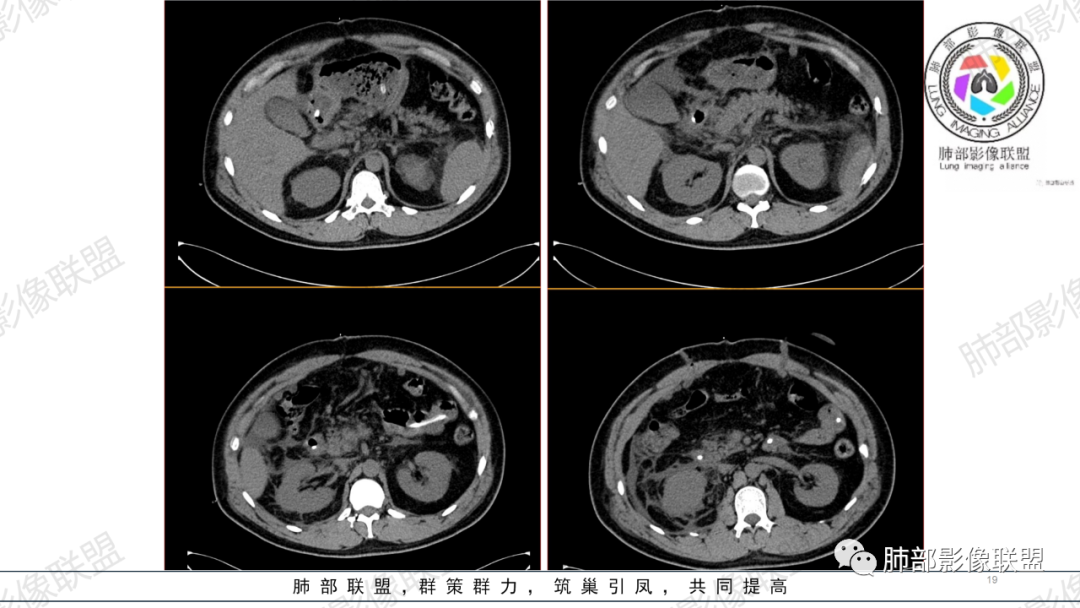

支气管痰栓或粘液阻塞,临床上并不少见,本例患者有腹部手术或胸部外伤肋骨骨折病史,其原因多是长时间采取一种被动体位,因怕疼痛而不敢咳嗽导致痰液引流不畅,自主排痰有一定的困难,导致痰液形成后不能及时排除。滞留痰液集聚形成痰块,混合坏死组织,部分形成痰栓。痰栓附着在气道壁上,局部气道变窄,如果不及时通畅气道,导致原来肺部、胸腔病变加重或出现新的病变,严重者可致局部气道闭塞,相应的肺叶出现肺不张CT上支气管粘液栓形态多样,可呈圆形,类圆形,条状、指套状、葡萄串状等。